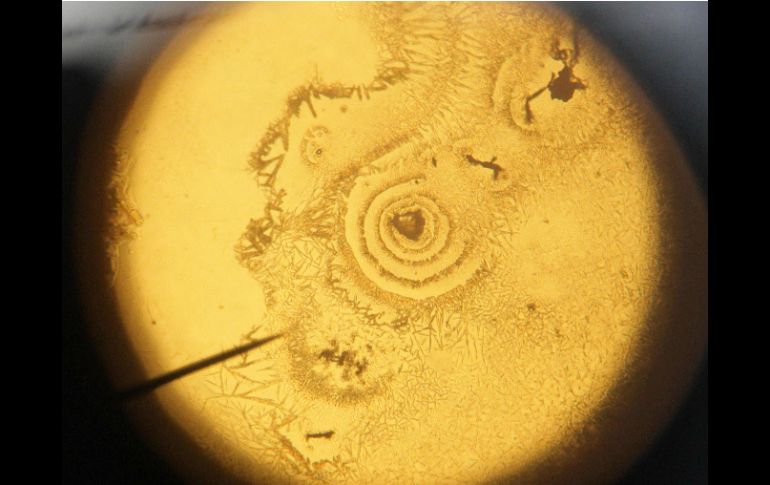

Tecnología | Por su aspecto externo no es amenazador por lo que el sistema inmunitario no la ataca Hallan nanopartícula que oculta un alérgeno para tratar el asma Por su aspecto externo no es amenazador por lo que el sistema inmunitario no la ataca Por: EFE 22 de abril de 2016 - 16:55 hs La nanopartícula podría emplearse también contra alergias alimentarias. EFE / ARCHIVO MADRID, ESPAÑA (22/ABR/2016).- Como si se tratara de un caballo de Troya, un equipo de científicos ha usado una nanopartícula biodegradable para tratar el asma, una tecnología que podría emplearse también contra alergias alimentarias, por ejemplo a los cacahuetes. En un nuevo enfoque para tratar el asma y las alergias, la nanopartícula oculta en su interior un alérgeno pero su aspecto externo no es amenazador por lo que es capaz de convencer al sistema inmunitario para que no la ataque, según estudio de la Northwestern University (EU) El estudio, que publica hoy la revista PNAS, indica que de esta manera se suprime a largo plazo la reacción alérgica que se produce en las vías aéreas ante un agente extraño y así se previenen los ataques de asma. Esta tecnología, según los expertos, puede también emplearse en las alergias causadas por los alimentos y, de hecho, la nanopartícula está siendo ya probada en un modelo con ratones alérgicos a los cacahuetes, que es similar a la que sufren los humanos. El autor principal del estudio Stephen Miller de la Nortwestern University explicó que este descubrimiento "supone una forma a largo plazo novedosa, segura y eficaz para tratar y potencialmente 'curar' a pacientes que sufren alergias respiratoria y alimenticias que pueden amenazar su vida". Esta es la primera vez que este método para crear tolerancia en el sistema inmunitario se emplea en alergias, aunque ya se está usando en test preclínicos para enfermedades autoinmunes, entre ellas la esclerosis múltiple, además de para las dolencias celíacas. Se trata de "un tratamiento universal" pues dependiendo de la alergia que se quiera eliminar es posible cargar la nanopartícula con polen de ambrosía o con proteína de cacahuete, según explicó el experto. La nanopartícula que se convertirá en caballo de Troya para 'engañar' al sistema humanitario y librarse de su ataque está compuesta de un biopoímero llamado PLGA -aprobado por la Administración de Alimentos y Medicamentos de Estados Unidos- que incluye ácido láctico y ácido glocólico. Cuando la nanopartícula cargada con el alérgeno se inyecta en el torrente sanguíneo de un ratón su sistema inmunitario no reacciona pues la partícula parece un desecho inocuo el cual es eliminado por un macrófago -un tipo de glóbulo blanco que fagocita el material extraño en el cuerpo-. "La célula aspiradora (en referencia al macrófago) presenta el alérgeno o el antígeno al sistema inmunitario diciendo: 'no os preocupéis esto es de aquí'", por lo que este detiene su ataque y se normaliza, explicó Miller. Durante el experimento los roedores fueron tratados para ser alérgicos a la proteína de la cáscara de huevo, por lo que ya tenían en la sangre anticuerpos y cuando volvieron a exponerlos a esta tuvieron una reacción alérgica parecida al asma. Sin embargo, tras ser inyectarles la nanopartícula no presentaron ninguna respuesta alérgica. Temas Estudios científicos Descubrimientos Ciencia médica Particulas Lee También Estudio chino revela una mutación que eleva riesgo de alzhéimer ¿Cómo se forman los recuerdos en la mente? La tendencia a hacer ejercicio se trasmite de padres a hijos y esta es la explicación de la ciencia Julieta Fierro será homenajeada en la FIL Recibe las últimas noticias en tu e-mail Todo lo que necesitas saber para comenzar tu día Registrarse implica aceptar los Términos y Condiciones